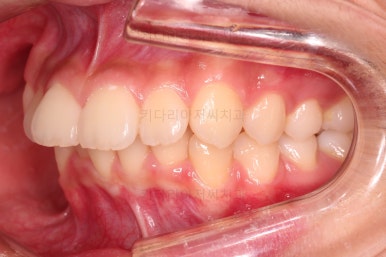

부산치아교정치과 키다리아저씨치과에서 마무리한 입안의 모습입니다.

가지런하게 잘 정렬이 되었고요.

윗니만 발치한 편악발치교정이지만 틈새 없이 공간이 닫혔으며 교합도 잘 맞습니다.

위아랫니가 가지런하게 보기 좋게 배열이 되었고요.

아랫니까지 윗니를 넣음으로써 튀어나와 보이던 앞니의 느낌이 좋아졌습니다.

물론 작은 아래턱에 맞춰 윗니를 뒤로 집어넣어야 해서 자칫 지나치게 들어간 입이 될까 염려되는 조심스러운 케이스였지만, 편악발치를 통해 최소한으로 입을 넣으면서 굉장히 조화롭게 잘 마무리 했습니다.

웃을 때 보이는 앞니의 느낌과 위치가 참 좋아졌네요.

옆 라인도 움푹 들어가 있던 아랫입술 아랫 부분이 완만하게 펼쳐지면서 입매도 많이 좋아졌습니다.